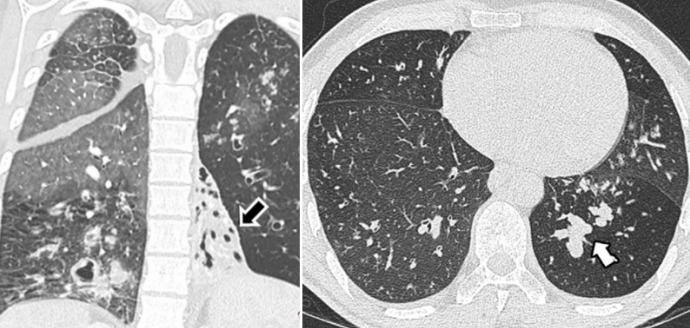

间质性肺疾病也是原发性免疫缺陷病的肺部表现之一,临床上10%~20%的CVID患者仅仅被诊断为ILD[27],而忽视了其背后真正的病因。在一项针对CVID的研究中,患者经肺活检证实均患有ILD,近2/3的患者存在脾大和淋巴结肿大。影像上所有患者都有大量的肺部结节(图3)[27]。在针对CVID伴非感染性肺部并发症的研究中,患者被分为无肺部疾病组、慢性呼吸道症状且无弥漫性影像学异常组、肉芽肿性淋巴细胞性间质性肺病(granulomatous lymphocytic interstitial lung disease,GLILD)组和ILD组,其中GLILD组相较于其他组别预后更差,且GLILD与呼吸困难、肺实变、玻璃影、网状影及低CD3+/CD8+细胞亚群相关[28]

图片

图3  45岁男性患者,CVID(肉芽肿性淋巴细胞间质性肺疾病)。肺部CT提示上叶(左)和下叶(右)实变灶和边界不清的结节(楔形箭头),小叶间隔增厚(白实箭头)和磨玻璃影(黑实箭头)[26]

图片来源:Imaging Features of Primary Immunodeficiency Disorders (DOI: 10.1148/ ryct. 2021200418)